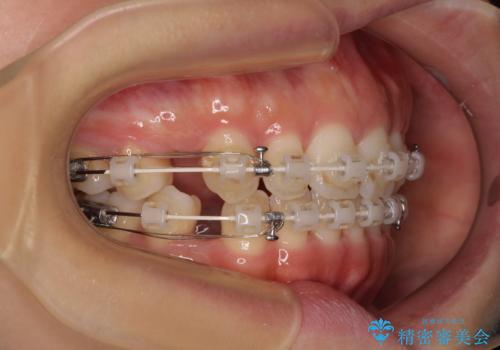

- 審美装置

- 1年8ヶ月

- 10-30回

舌の突出癖を改善するためのトレーニングをしっかりと行っていただいたことで、比較的スムーズに治療を進めることができました。